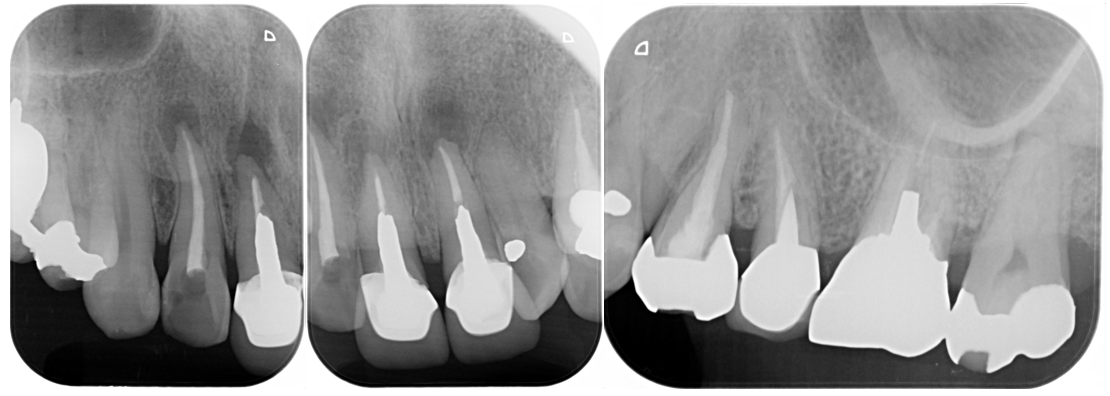

症例2

BEFORE |

AFTER |

| 患者様データ | 80代 男性 |

| 来院時の主訴 | 「右上の奥歯が噛むと痛い。」 |

| 医院の診断 | 虫歯の再発、慢性根尖性歯周炎、炎症による歯髄狭窄 |

炎症を起こしてからかなり時間が経っているためか、神経が確認できない程に歯髄狭窄を起こしていました。 ラバーダム防湿とマイクロスコープを使用して丁寧に治療を行いました。 再根管治療のため、殺菌性があり歯を補強することのできる根管充填材料を使用しています。 |